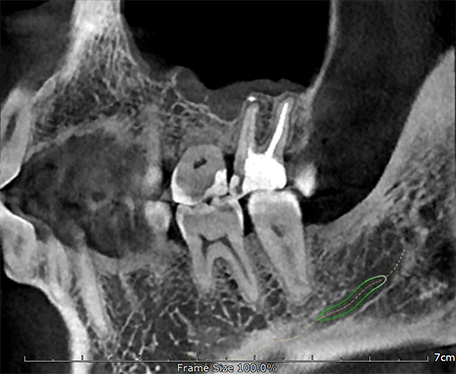

Алгоритм уменьшения вторичного излучения от металлов

Умная Функция Уменьшения Артефактов от Металла (Smart Metal Artifact Reduction Function) – позволяет минимизировать артефакты от вторичного излучения металлов и получить необходимую диагностическую информацию для постановки корректного диагноза, а также планирования и контроля проведенного лечения.

SMARF - алгоритм уменьшения вторичного улучшения от металлов дентального компьютерного 3D томографа.jpg